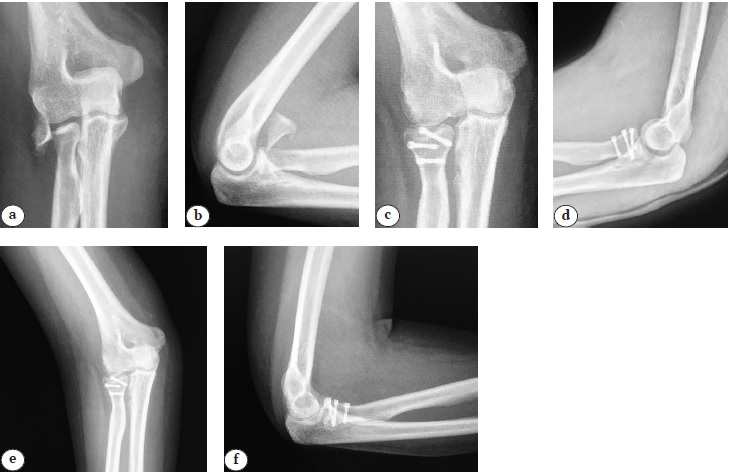

У 11 (11%) пациентов было выявлено 14 осложнений, а у 24 пациентов сохранялись значимые ограничения амплитуды движения (табл. 4). Несращение перелома после остеосинтеза наблюдалось в 4 случаях. Все пациенты прооперированы повторно: 3 пациентам выполнено эндопротезирование ГЛК, одному пациенту — резекция. Вторичное смещение отломков произошло у 3 пациентов: в 2 случаях через 6 и 8 мес. после остеосинтеза потребовалось выполнение повторной операции — удаление пластины, винтов, частичная моделирующая резекция ГЛК, один пациент отказался от повторной операции. У 2 пациентов диагностирована периимплантная инфекция по прошествии 1 и 4 мес. после остеосинтеза. В обоих случаях выполнены ревизия, санация, резекция отломков ГЛК. Инфекционный процесс был купирован у обоих пациентов. У 2 пациентов развилась гетеротопическая оссификация ЛС, в одном случае потребовавшая выполнения повторной операции через 6 мес. после первичной в объеме резекции оссификатов, удаления винтов (рис. 2).

Рис. 2. Гетеротопическая оссификация локтевого сустава у пациента с оскольчатым переломом головки лучевой кости типа Mason III после остеосинтеза пластиной и компрессионными винтами:

а — рентгенограмма в прямой проекции до остеосинтеза; b — после остеосинтеза; c, d — через 6 мес. после остеосинтеза: обширная оссификация локтевого сустава; e, f — трехмерная реконструкция локтевого сустава, выполненная на основе КТ; g, h — рентгенограммы после резекции оссификатов. В ходе выполнения повторной операции были резецированы оссификаты, являющиеся причиной ограничения движений в локтевом суставе. Оссификаты, располагающиеся под коллатеральными связками, не резецировались по причине высокого риска их повреждения

Figure 2. Elbow heterotopic ossification in a patient with Mason type III comminuted radial head fracture after osteosynthesis with a plate and compression screws:

a — X-ray in a direct projection before osteosynthesis; b — after osteosynthesis; c, d — 6 months after osteosynthesis, extensive elbow ossification is observed; e, f — three-dimensional reconstruction of the elbow joint performed on the basis of CT; g, h — X-rays after resection of ossifications. During the re-operation, the ossifications responsible for the limited range of motion in the elbow were resected. Ossifications under the collateral ligaments were not resected due to the high risk of their damage